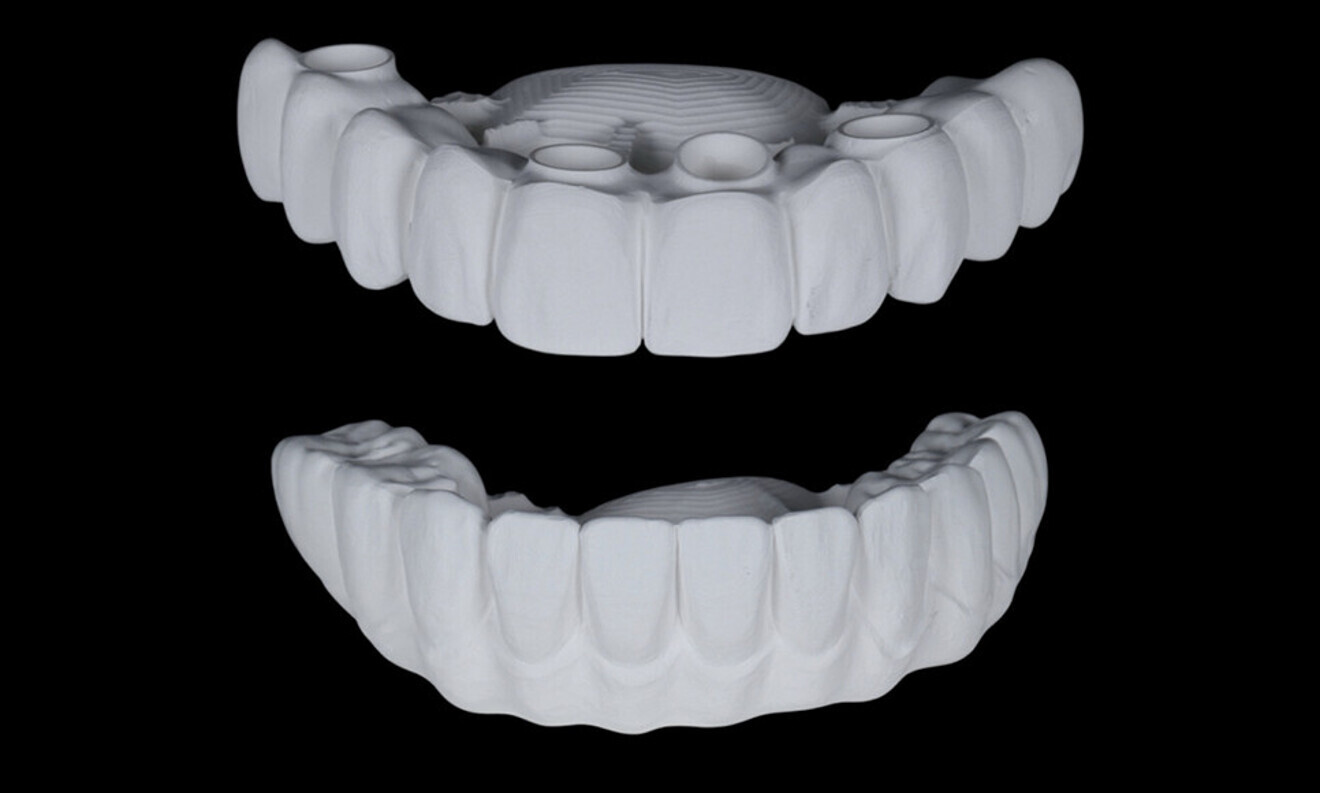

After a healing period of five months and successful osseointegration, the process for the definitive restorations was initiated. The chosen material was milled monolithic zirconia, and Variobase final abutments was used, placed on the screw-retained abutments to ensure excellent stability and retention of the definitive restorations (Figs. 69–75).

Figs. 69–75: The definitive restorations were fabricated after a five-month healing period